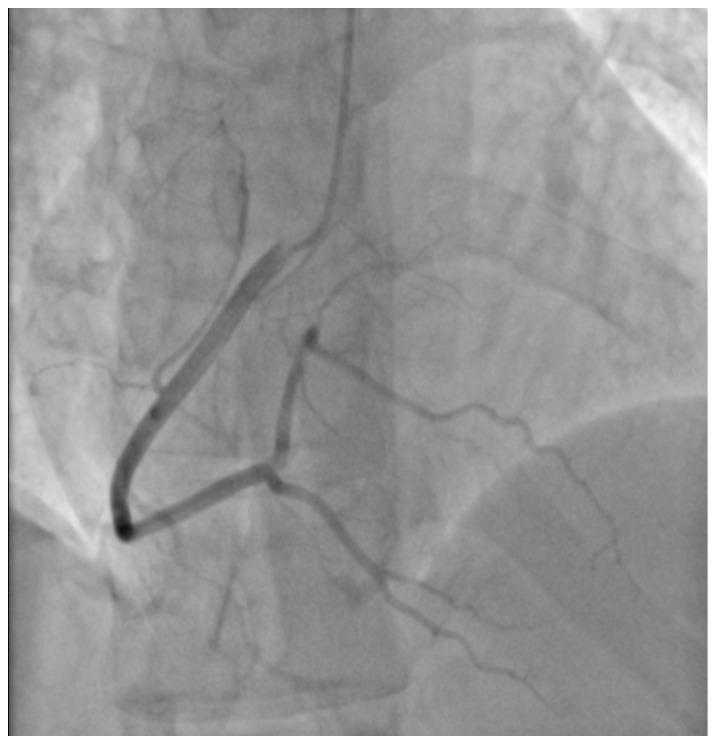

This article presents the case of a 29-year-old male patient, addicted to prescribed medical marijuana administered for mixed anxiety and depressive disorder and without classic cardiovascular risk factors and history of myocarditis, suffering from episodes of paroxysmal hemodynamically unstable ventricular tachycardia. Cardiovascular magnetic resonance imaging of the heart revealed disseminated non-ischemic myocardial injury lesions of subepicardial and intramuscular location. Additionally, the individual experienced myocardial infarction without ST segment elevation following marijuana intake. Treatment required implantation of a cardioverter-defibrillator and ablation of the myocardial areas responsible for the origin of the arrhythmia, as well as appropriate pharmacotherapy and marijuana addiction treatment.

本文介绍了一名29岁男性患者的病例,该患者因混合性焦虑和抑郁障碍而服用处方医用大麻成瘾,无典型心血管危险因素及心肌炎病史,却出现阵发性血流动力学不稳定的室性心动过速发作。心脏心血管磁共振成像显示,心外膜下和肌内有散在的非缺血性心肌损伤病灶。此外,该患者在吸食大麻后发生了无ST段抬高的心肌梗死。治疗需要植入心脏复律除颤器,消融导致心律失常起源的心肌区域,并进行适当的药物治疗和大麻成瘾治疗。